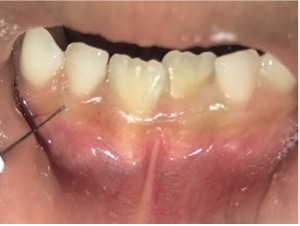

En el examen clínico intraoral, se observó dentición mixta, todos los dientes limpios, sin embargo, con maloclusión, por esa razón el paciente fue referido para evaluación y tratamiento ortopédico. Conforme la mamá había reportado, los incisivos laterales primarios inferiores estaban en oclusión (Figura 1) y sin movilidad. A través de la radiografía periapical en la región de los incisivos laterales inferiores (Figuras 2 y 3), fue observado que los gérmenes de los incisivos laterales inferiores permanentes se encontraban en la etapa 8 de Nolla, entonces, deberían estar estallando en la cavidad oral.

Figura 1: Fotografía intraoral oclusal de la arcada inferior: Se observa la presencia de los incisivos laterales primarios inferiores.